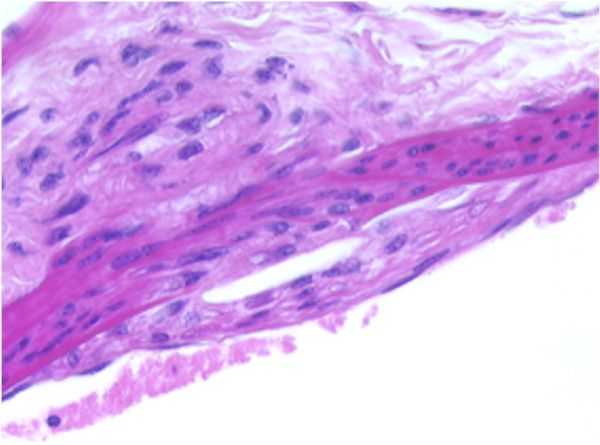

AORTA-a

AORTA–a: Stain: Elastic Fiber. F19-01

Early Atherosclerotic plaque formation, tunica intima, thoracic aorta.

Representation of an accumulation of lipoid filled or foam cells of the xanthomatous type occupying and expanding the subendothelial space, effectively separating the endothelial cell layer from the internal elastic membrane of the tunica intima. The wall of the aorta is mildly thickened by this accumulation of material and the internal elastic membrane appears to be intact within this segment.

This response represents early atherosclerotic plaque formation localized within the tunica intima. The rest of the artery appears to be within normal limits.